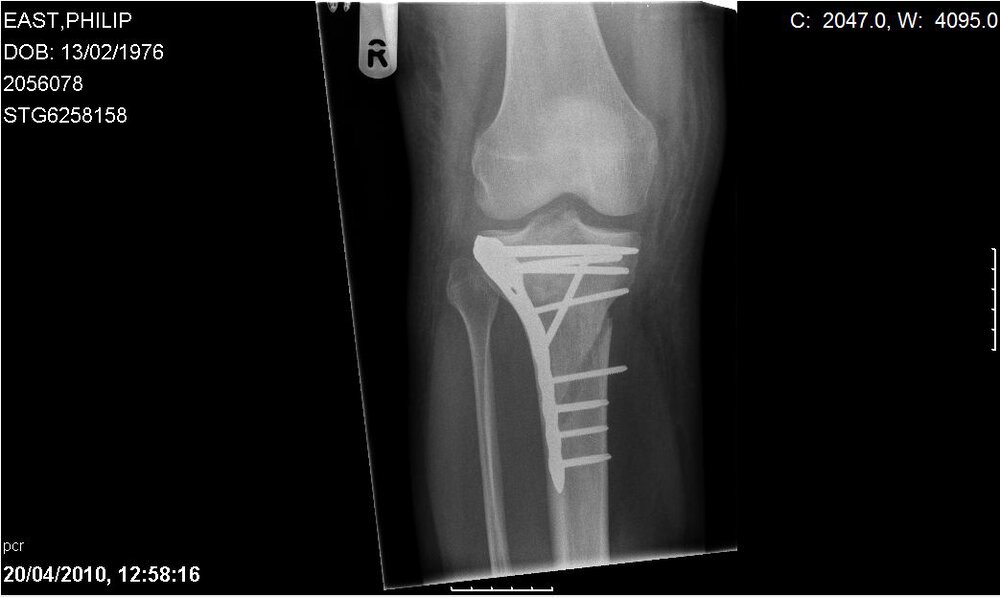

8. Whadda ya reckon. Would you go boarding with this in your knee when its healed. Or am I being stupid. So worried that flying days are over....

10. Hey all. Went out for an hour last monday before work started and got picked up by a gust and landed on my knee. End result I have fractured my tibia and also the plateau in my knee joint. Now have plates and pins in the knee, one monster "chick pulling" scar and 3 months with no weight on my leg allowed and a significant chance of arthritus in the knee later on. Anyone done this and how did you get on? Reckon my boarding days are over. Maybe time to buy a buggy? Had knee pads on and luckily have no other injures, not even a scratch. Big lesson though. Always wear a helmet. I wasn't as the wind wasn't that strong, but having seen what can be done to a leg bone, your nut doesn't have a chance. And also, always carry on phone on you. I was out on my own in the park and was able to call for an ambulance, but no help from the public, not that I asked, but having a phone on me saved the day. Keep safe peeps.